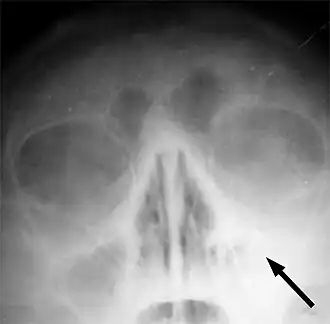

Рентгеновский снимок пазух больного гайморитом (стрелкой обозначено затемнение в области верхнечелюстной пазухи, указывающее на присутствие в ней жидкости)

Одним из основных симптомов гайморита является тянущая боль, которая возникает при наклоне туловища вперёд. Подтверждение диагноза производится на основании рентгеновского снимка.